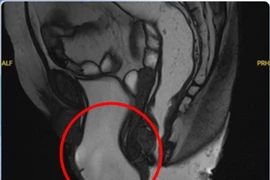

Khối sa sàn chậu đã được xử lý triệt để, không còn gây cản trở trong sinh hoạt, đồng thời tình trạng rối loạn tiểu tiện cải thiện rõ rệt so với trước mổ.

Chịu đựng 20 năm, cụ bà 82 tuổi sa toàn bộ sinh dục ra ngoài

​Sa sinh dục là bệnh lý thường gặp ở phụ nữ, có thể phòng ngừa và điều trị dứt điểm nếu được phát hiện sớm.